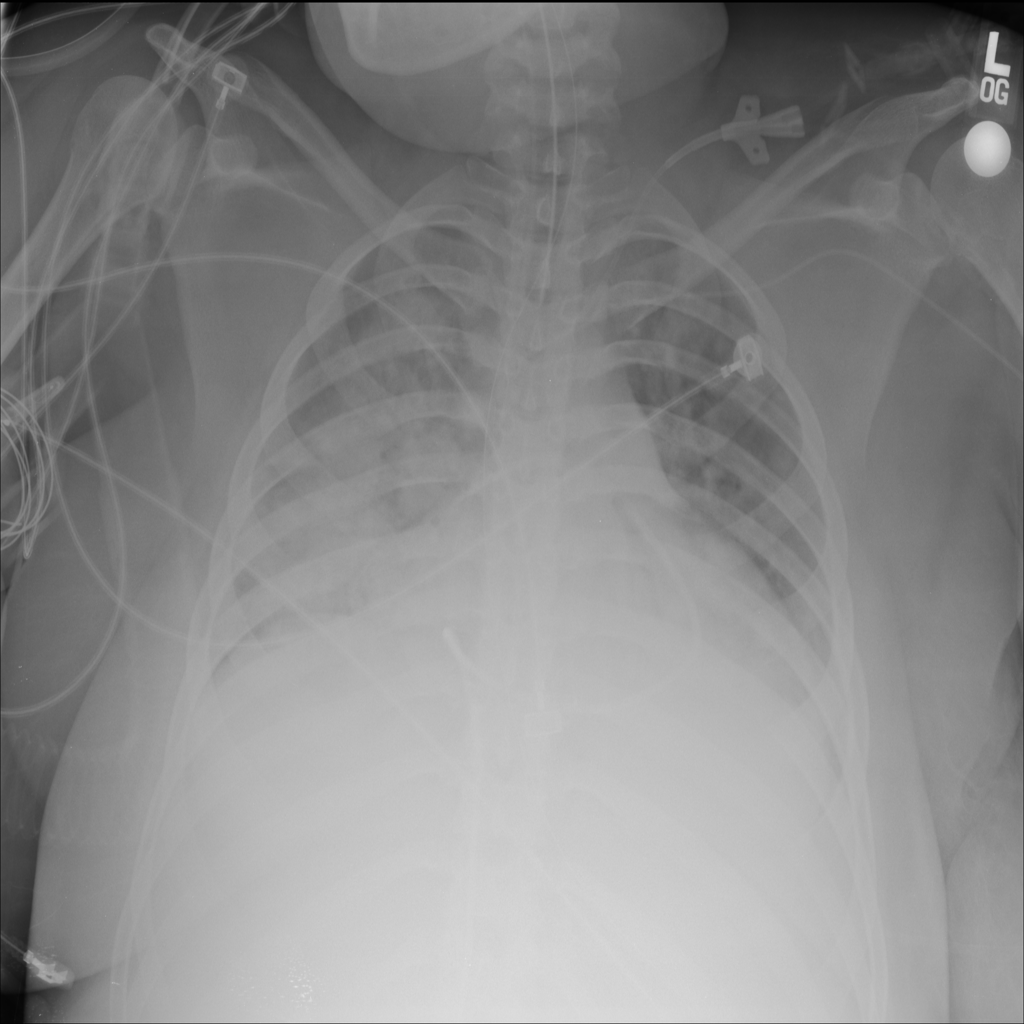

PAT-E828 · IMG-004Edema

PAT-E828 · IMG-004

AP